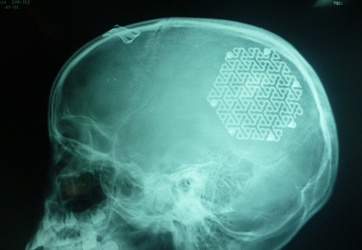

Với phương pháp tạo hình hộp sọ bằng tấm kim loại (titanium), các bác sĩ Bệnh viện Hữu nghị Việt Nam - Cu Ba Đồng Hới đã phẫu thuật tái tạo thành công hộp sọ cho bé gái 9 tuổi ở xã...